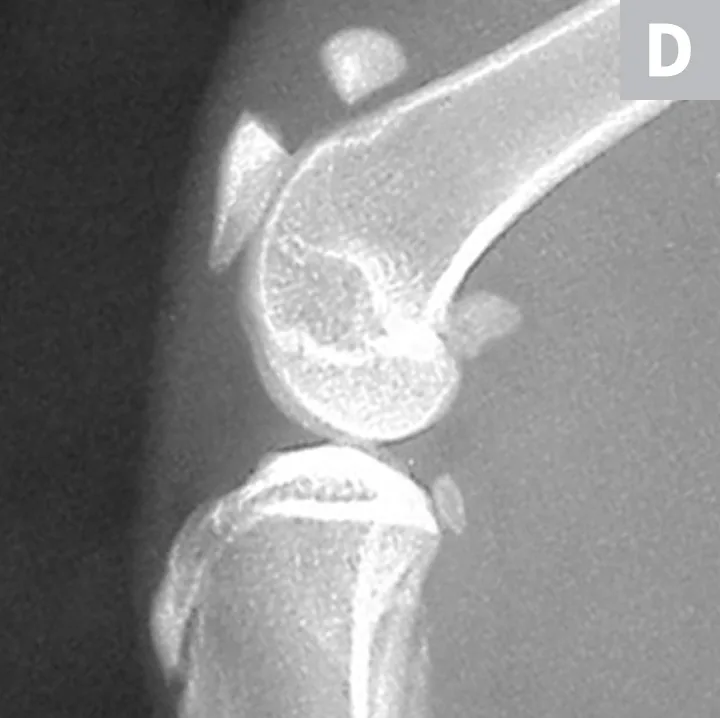

Serial radiographs of the pelvic limbs were taken periodically to monitor progression of the patellar fractures. Comparative orthopedic radiographs (Figure 3) 2 and 8 years after initial presentation revealed persistence of patellar fractures, with fragmentation, progressive sclerosis, and osteophytosis of the left patella.

Radiographs of the patellar fractures taken 2 years (A, left stifle; B, right stifle) and 8 years (C, left stifle; D, right stifle) after initial presentation. Progressive fragmentation and osteophytosis of the left patella and displacement of the right patellar fragments can be seen.